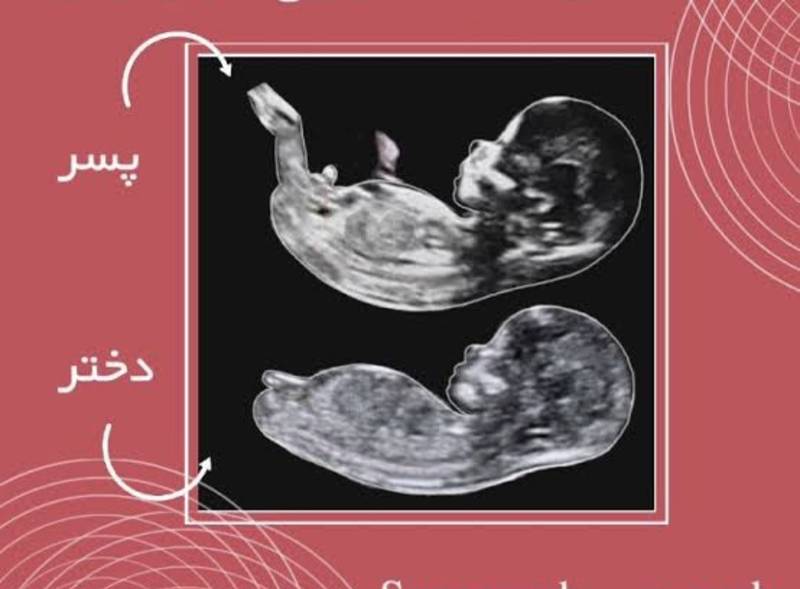

در جنین پسر، هورمون تستوسترون از هفته هفتم بارداری ترشح خود را آغاز میکند که سبب پیدایش آلت تناسلی و بیضهها میشود. این بیرون زدگی با نطفه برآمده در روزهای اولیه تکامل جنین متفاوت است و تشخیص پسر یا دختر بودن در مراحل ابتدای بارداری وجود ندارد.تعیین جنسیت دختر

در سونوگرافی تعیین جنسیت، متخصص زنان اگر علامتی با اصطلاح همبرگر مشاهده کند یعنی جنسیت جنین دختر است. برآمدگی کلیتوریس و آلت مردانه در مراحل ابتدایی بارداری تقریباً به یک اندازه است و به همین دلیل توصیه میشود که برای این سونوگرافی حتماً در زمان مناسب خود مراجعه نمایید.